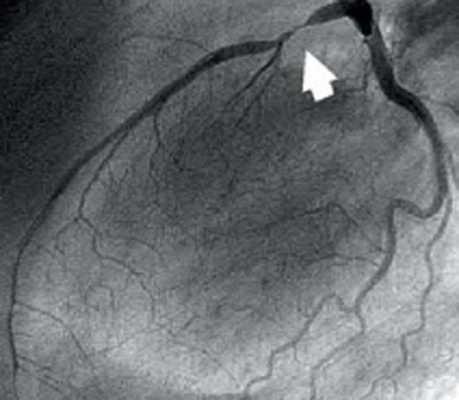

Большинство пациент имеют плохой прогноз в связи с диффузной органной недостаточностью, обусловленной генерализированным атеросклерозом.Коронароангиография

![]()

В университетскую программу первых курсов входит изучение строения сердца и его коронарных сосудов. Но чаще всего авторы учебников ограничиваются описанием только крупных сосудов. Клиницисты же используют совершенно иную, но также международную номенклатуру. Коронароангиография и имплантация стентов требуют более подробного описания сосудов сердца, что нашло применение и в международной практике.

Из курса анатомии каждый узнал, что от аорты отходят две артерии, кровоснабжающие само сердце: левая и правая коронарные артерии. Утолщения на корне аорты, из которых и выходят эти артерии, называются соответственно левым и правым коронарными синусами.

Выделяют следующие части левой коронарной артерии (LCA, left coronary artery): главный ствол, который делится на переднюю межжелудочковую ветвь (ramus interventricularis anterior, RIVA или left anterior descending, LAD), а также огибающую артерию (left circumflex coronary artery, LCх).

Главный ствол этой артерии длиной редко превышает 1 см, а далее делится на две свои конечные ветви. Передняя межжелудочковая ветвь располагается на передней поверхности сердца вплоть до его верхушки. На своем протяжении от этой артерии отходят передние желудочковые ветви (диагональные ветви, RD/R.Diag) и передние перегородочные ветви. В коронароангиографии с целью топического указания места поражения предложено делить коронарное русло на сегменты.

Проксимальный сегмент ПМЖВ начинается своим ответвлением от ствола и продолжается до места отхождения от нее первой перегородочной или первой RD, средняя часть — до ответвления второй перегородочной ветви или второй RD, дистальная — до верхушки сердца/после отхождения второй RD.![]()

Огибающая артерия всегда располагается на задней поверхности сердца. В ее проксимальной части от нее отходит ветвь тупого края (obtuse marginal artery, obtuse marginal branch, OMB). В зависимости от места этого ответвления различают проксимальную и дистальную части огибающей ветви. Очень редко от главного ствола между передней межжелудочковой ветвью и огибающей ветвью посередине отходит еще одна ветвь, берущая начало непосредственно из общего ствола — промежуточная артерия (RIM, ramus intermedius).

Выделяют следующие три части правой коронарной артерии (RCA): проксимальную (от устья до первого ее поворота, обычно располагающегося горизонтально), среднюю (от первого до второго поворота) и дистальную (после второго ее поворота до разделения артерии на ветви у «креста» сердца (crux cordis) — места пересечения задней межжелудочковой и атриовентрикулярной борозд сердца). Иногда непосредственно после самого устья от сосуда отходит маленькая ветвь — ветвь артериального конуса (ramus coni arteriosi, CB), а также много мелких ветвей к правому предсердию.

Самой главной из этих ветвей является артерия синоатриального узла (S-A node artery, SNA). Она часто располагается под правым ушком сердца. В редких случаях ветвь артериального конуса имеет собственное устье. Этот вариант всегда следует учитывать, поскольку при коронароангиографии можно принять эту артерию за главный ствол правой коронарной артерии. Перекрыв вход в эту артерию катетером, можно вызвать локальную ишемию и, как следствие, нарушения ритма вплоть до трепетания камер сердца. В передней части венечной борозды, в области острого края сердца, от правой коронарной артерии отходит ветвь острого края (acute marginal artery, AMB), чаще от одной до трех, которая в большинстве случаев достигает верхушки сердца.Итак, перечислим еще раз все сокращения: